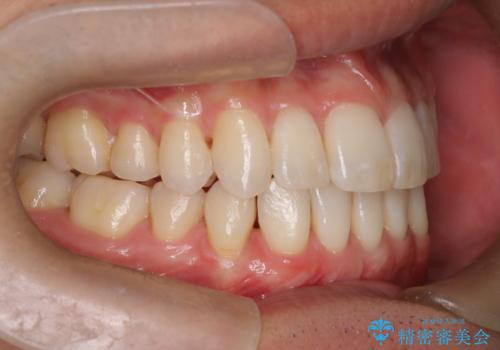

前歯の重なりとガタガタをマウスピースで改善した症例

初診時の歯並びの状態としては、上下ともに前歯部の中等度のがたつきがあり、上の前歯が重なっている状態でした。

また元々下の前歯は1本少なく、歯の本数が少ないことを前提とした矯正治療を行いました。

抜歯は必要なく、マウスピース矯正にて治療を行っています。